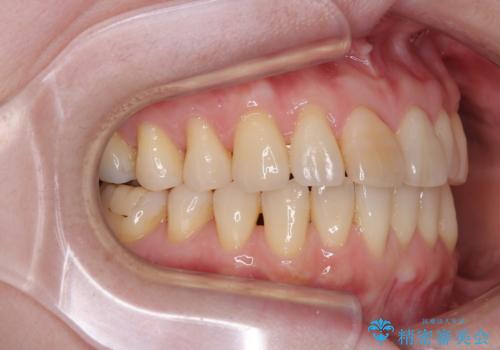

前歯のデコボコをインビザライン・モデレートで矯正治療

- 上下前歯のデコボコを気にして来院された患者様です。

安価なインビザラインパッケージを用いての治療を希望されており、デコボコの程度が中等度であったため、インビザライン・モデレートを用いて矯正治療を行うこととしました。

インビザライン・モデレートは、製作できるアライナーの枚数に制限があるため、移動可能な量に限りがあるものの、インビザライン・ライトよりも枚数が多いため、幅広い症例に対応可能です。